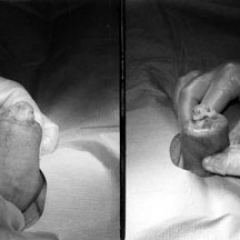

Existe todo un debate en torno a esta pregunta. Según indican algunos estudios, los individuos circuncidados tienen una menor probabilidad de sufrir una enfermedad venérea, incluyendo el sida. Esto ha hecho pensar a muchos que sería ideal operar a todos los varones. En opinión de otros autores, los individuos circuncidados experimentan una disminución en el placer sexual, y por eso no recomiendan esta cirugía, salvo en casos estrictamente necesarios.